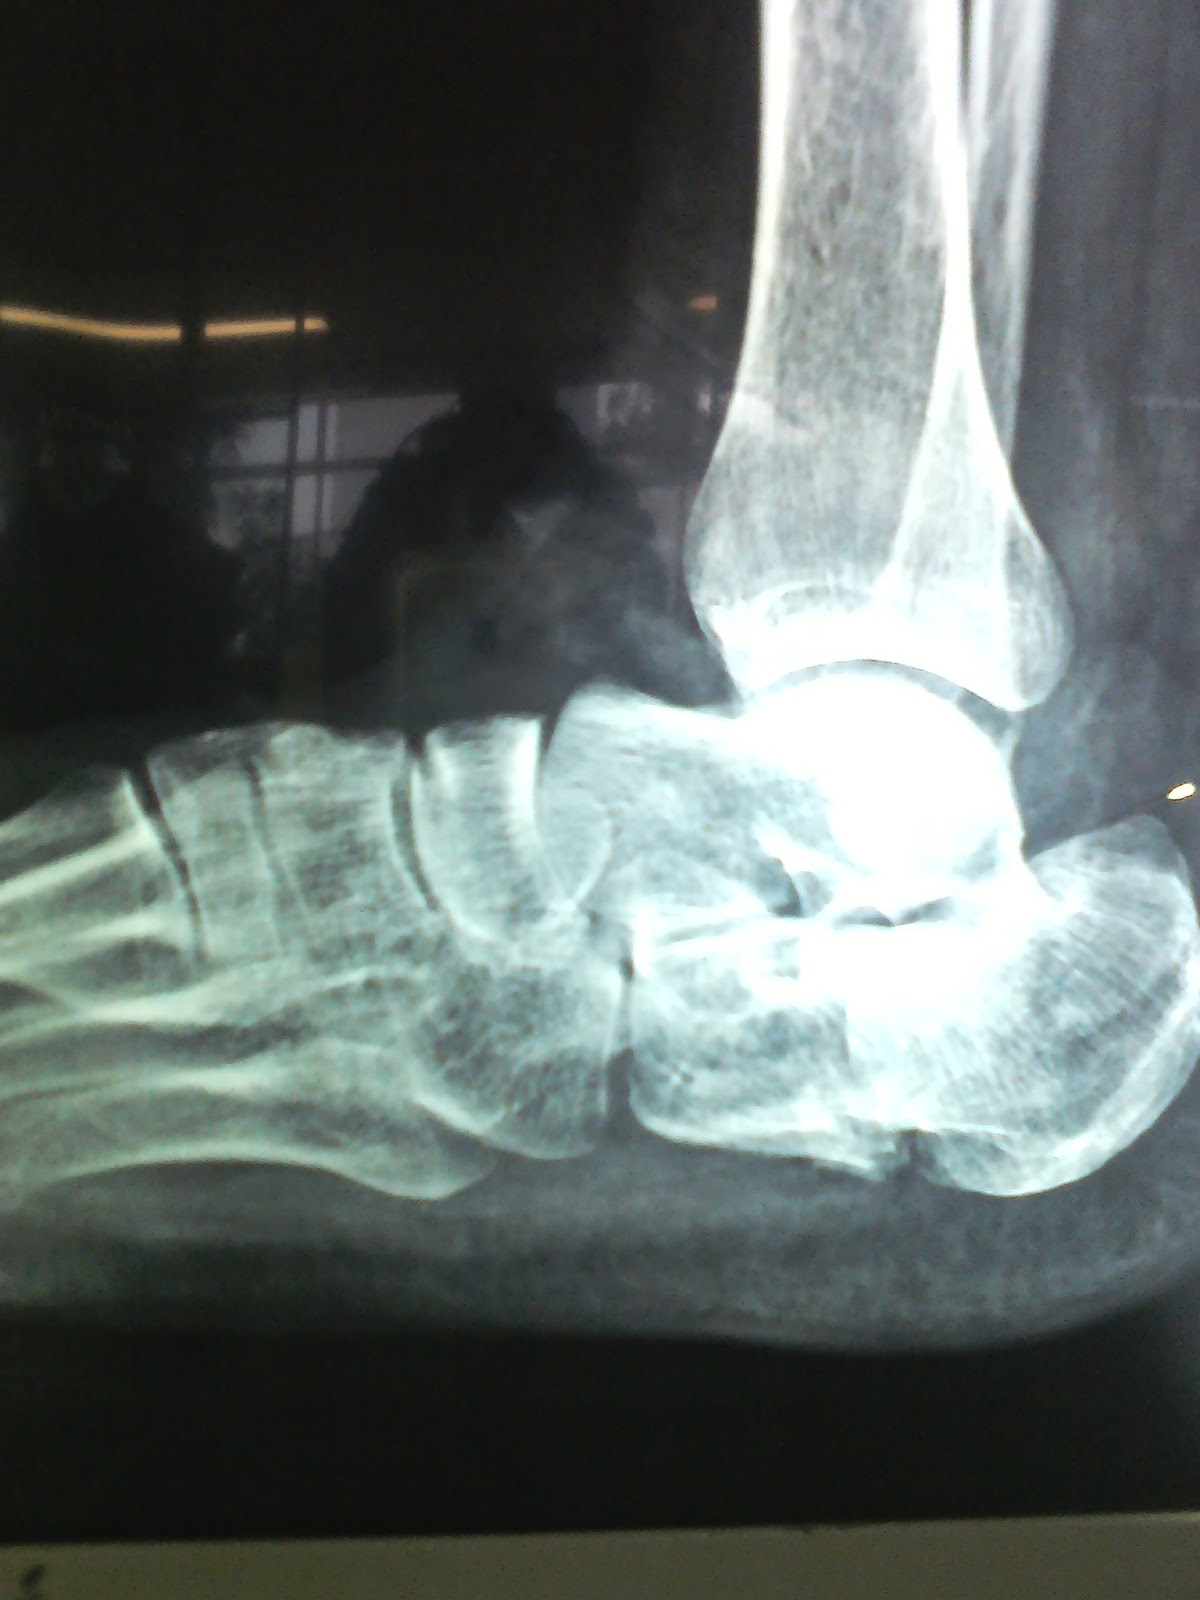

Fracturas de calcáneo: un verdadero reto.

Recuperación De Fractura De Calcaneo Foro. WebLa recuperación de la fractura de calcaneo es muy larga. Lo normal son unos 3 a 6 meses. Depende claro del tipo de fractura y del tipo de persona. Es recomendable. WebEjercicios de recuperación de fracturas de calcáneo El tratamiento inicial de la fractura de calcáneo consiste en utilizar un zapato perfecto para un pie fracturado . Estos zapatos.

WebLa recuperación de una fractura de calcáneo puede ser larga. Se le colocará una férula o una escayola. No debe poner peso en el pie durante al menos 6-8. WebEl primer paso para la recuperación de una fractura de calcáneo es descansar la pierna y el pie afectado. Esto significa limitar la actividad física y evitar cualquier actividad que.

WebEl día 4 de este mes de diciembre me operaron de la fractura de calcáneo ,aplastamiento , me pusieron 3 tornillos ,quería saber si a alguien le a pasado lo mismo y. WebTiempo de recuperación de una fractura de calcáneo sin cirugía El mejor calzado tras una fractura de calcáneo Algunas fracturas de calcáneo son evidentes y provocan. Webhttp://www.tuortopedista.comLa medicina ortopédica basada en evidencia, ahora en la webTUORTOPEDISTA.COM permite a través de un portal de internet el acceso ...

WebLas fracturas intraarticulares del calcaneo deben ser operadas a los pocos dias de haber ocurrido, para colocar todos los fragmentos en su sitio y restaurar las. WebNo está conectado. [Identificarme] Portada de PortalesMedicos.com » Foros » Foros Médicos » Foro Traumatología » Reconstrucción fracturas de calcáneo. Registrarme. WebTiempo de recuperación de la fractura del calcáneo Estaba pasando unas vacaciones estupendas en Mauricio, hasta que decidí que estaría bien volver a pasar por una ola en.